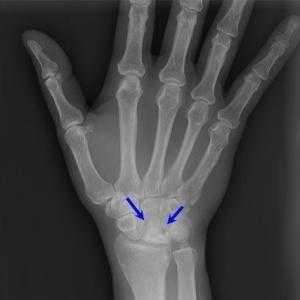

Болезнь Кинбека. Это остеонекроз полулунной кости запястья. В результате больших профессиональных нагрузок (например, у спортсменов) на лучезапястную кость происходит разрушение и некроз костной ткани. По мере прогрессирования болезни боль нарастает. На последних стадиях может развиться артроз суставов запястья.

Асептический некроз

Довольно серьезное заболевание, поражающее чаще кости запястья. Нарушается кровоснабжение костной ткани, что ведет к ее отмиранию, рассасыванию. Эта область воспаляется и становится очень болезненной и в состоянии покоя, и при нагрузках; появляется отек. Причины асептического некроза: перелом кости или же ее воспаление.

Болезнь Кинбека

Спровоцировать возникновение такого нарушения могут микротравмы, травмы и ушибы. Патология часто диагностируется у взрослых, чья профессия связана с физическим ручным трудом. Заболевание протекает в 4 стадии, при этом на начальных этапах затруднительно определить недуг, так как симптомы невыраженные. Но по мере прогрессирования наблюдается отвердевание костей и уменьшения их в размерах. Больной замечает, что сустав сильно опух, а при самых минимальных манипуляциях становится больно. Со временем припухлость становится большей, поражением затрагиваются соседние структуры, из-за чего возникает артроз запястья.